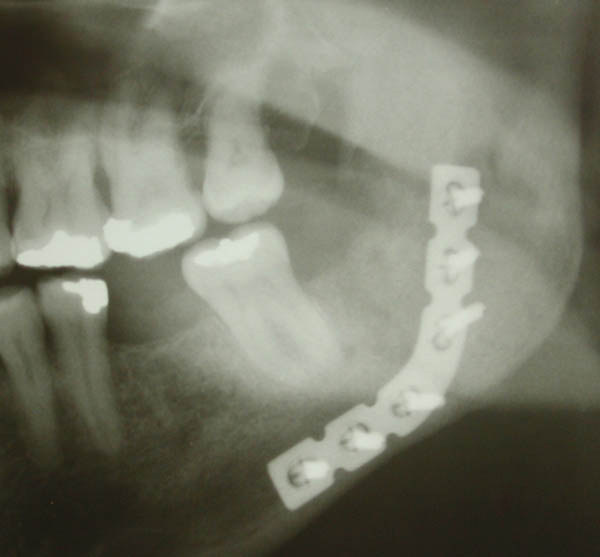

Fractured Jaw Plated